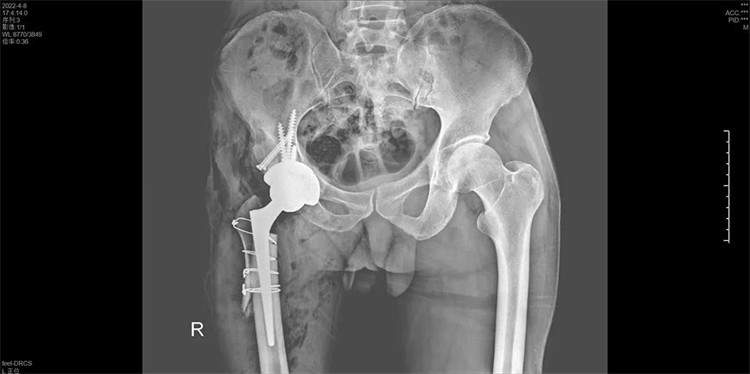

手術(shù)過程一氣呵成,手術(shù)歷時2個小時,出血200ML,順利地為周大伯進行了右側(cè)人工全髖關(guān)節(jié)置換術(shù),將人工髖關(guān)節(jié)準(zhǔn)確地安裝在周大伯的真臼內(nèi)并做了牢固的固定。術(shù)后第1天周大伯就已下地行走。